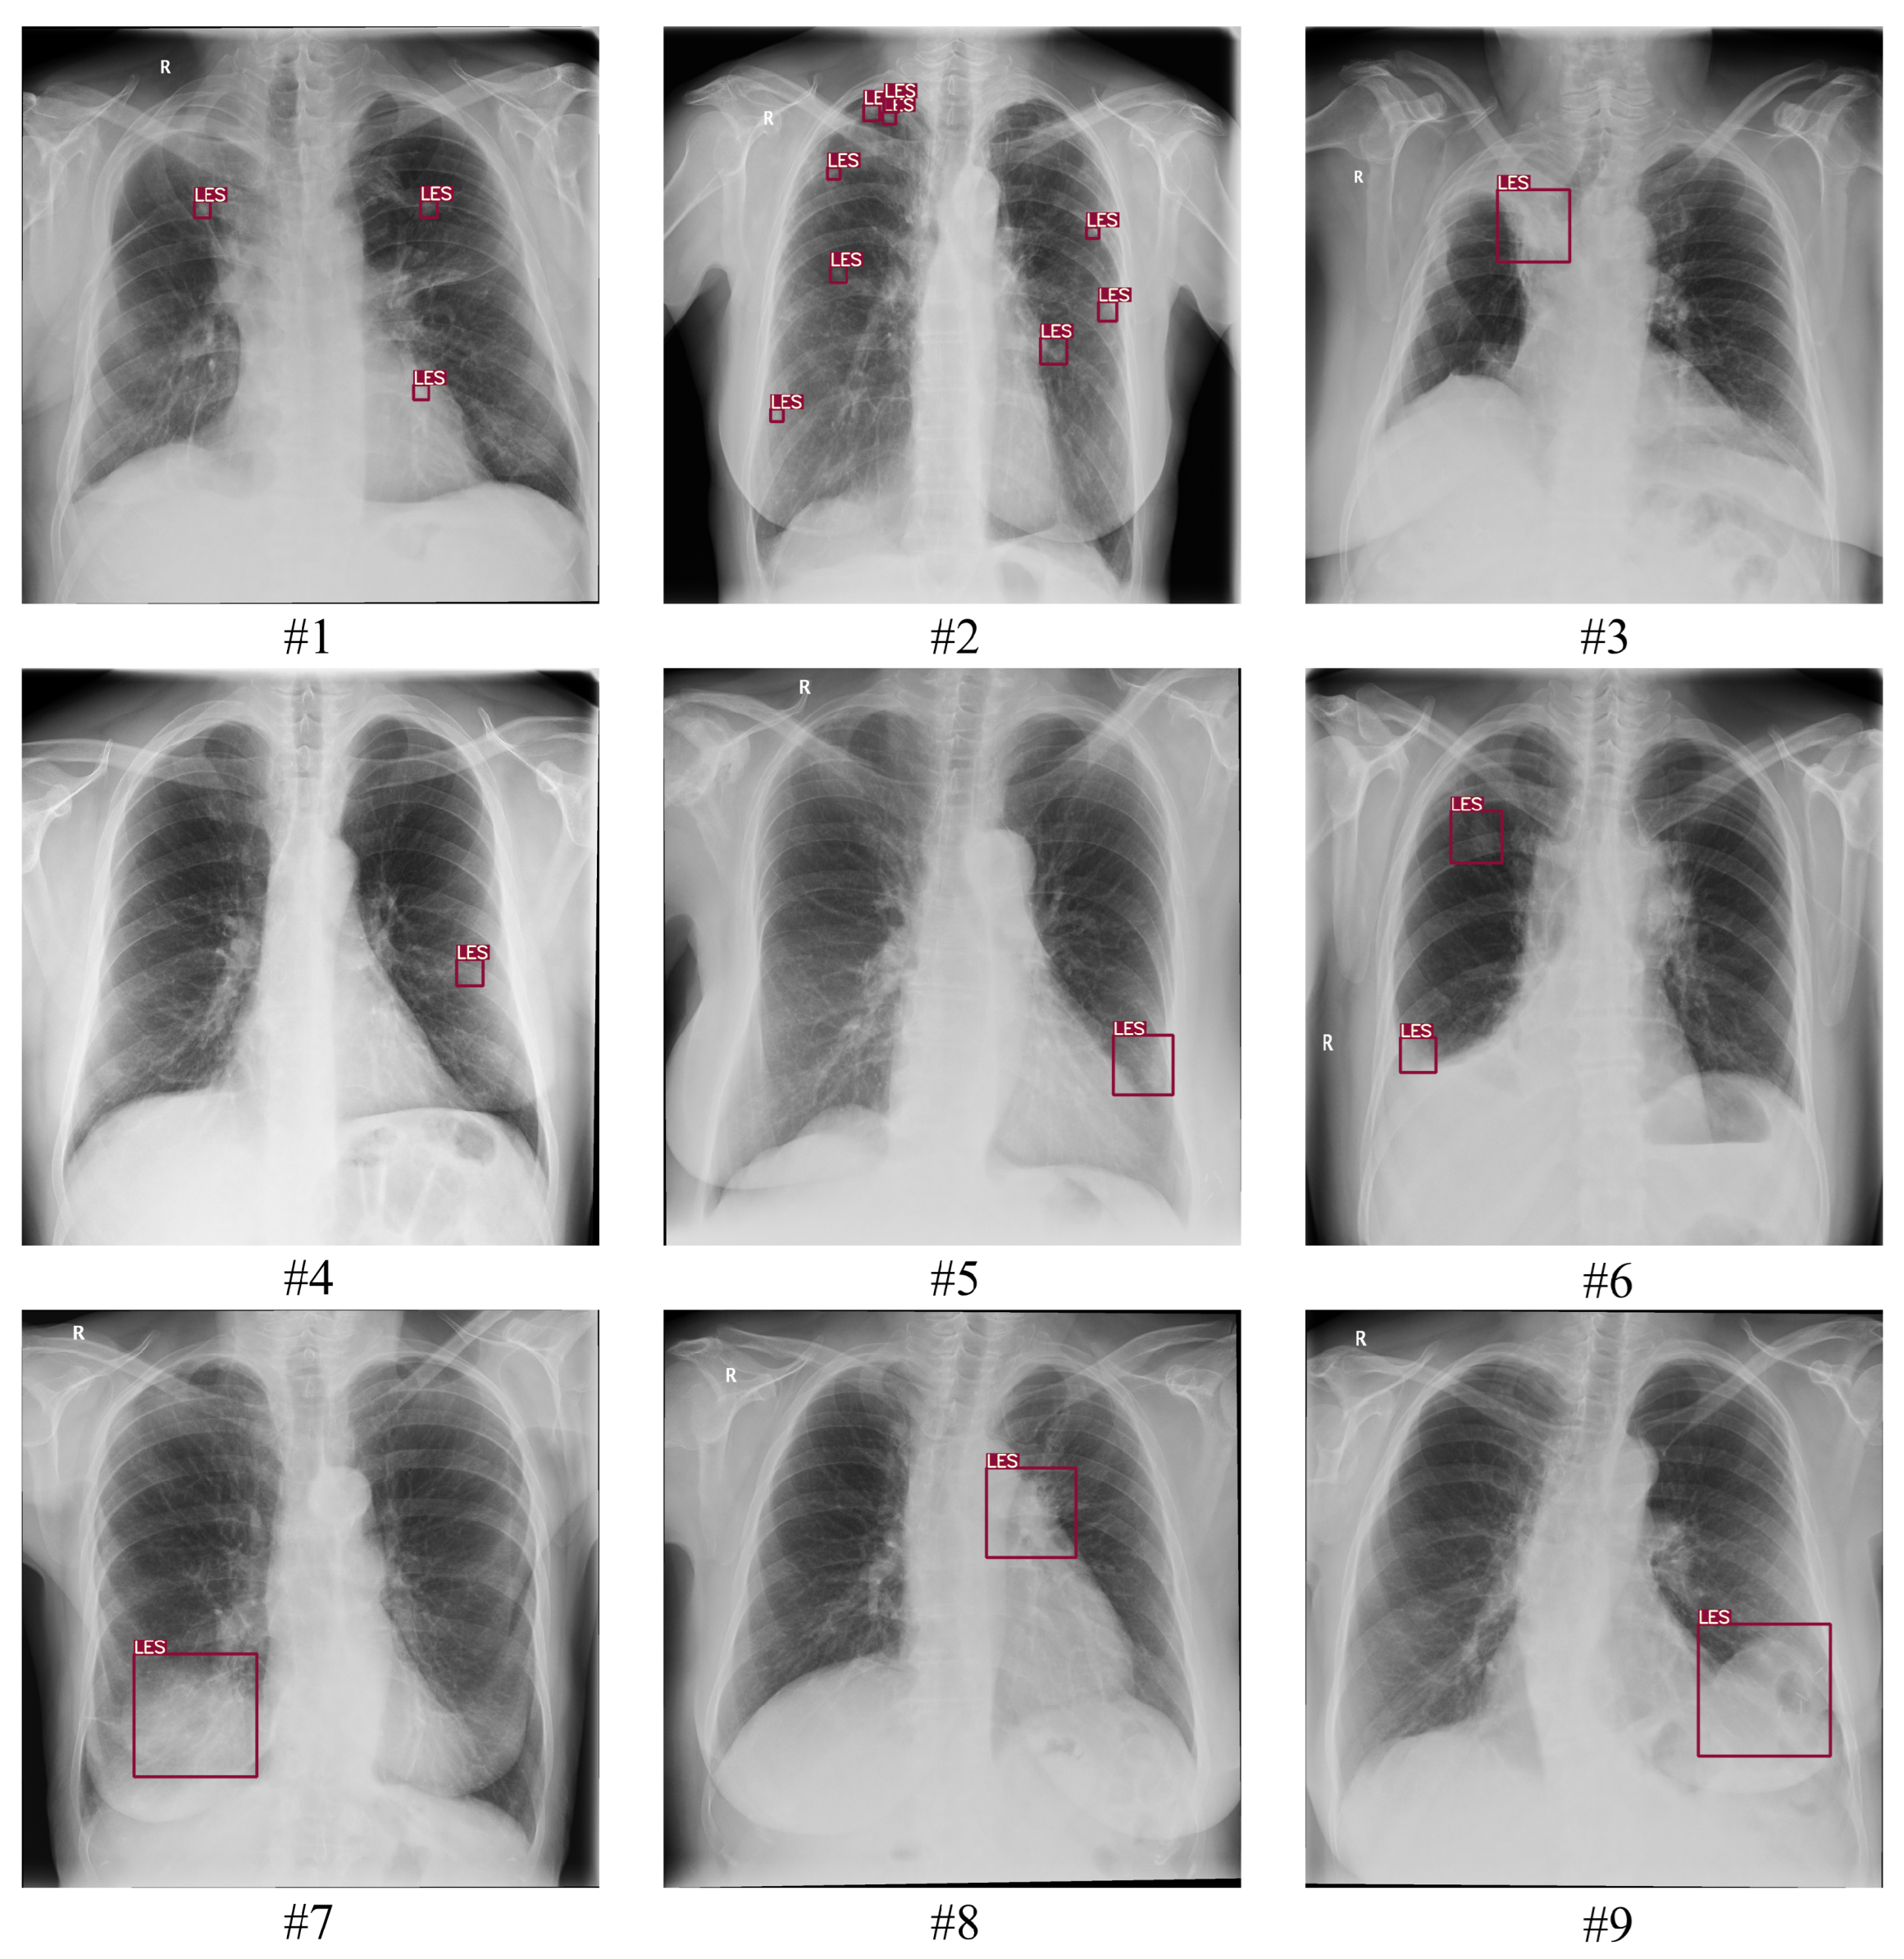

3.1. Software

3.1.1. Training Data

3.1.2. Model Architecture